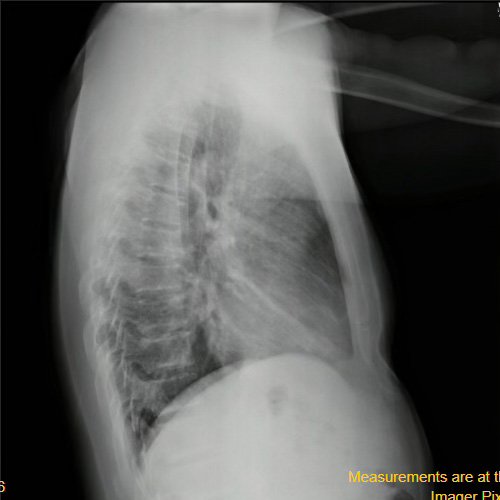

• Radiografía de tórax frente/perfil (día 3): rotada, índice cardiotorácico conservado, senos costofrénicos libres. Radiopacidad parahiliar derecha.

Radiografía de tórax frente y perfil. (día 3).